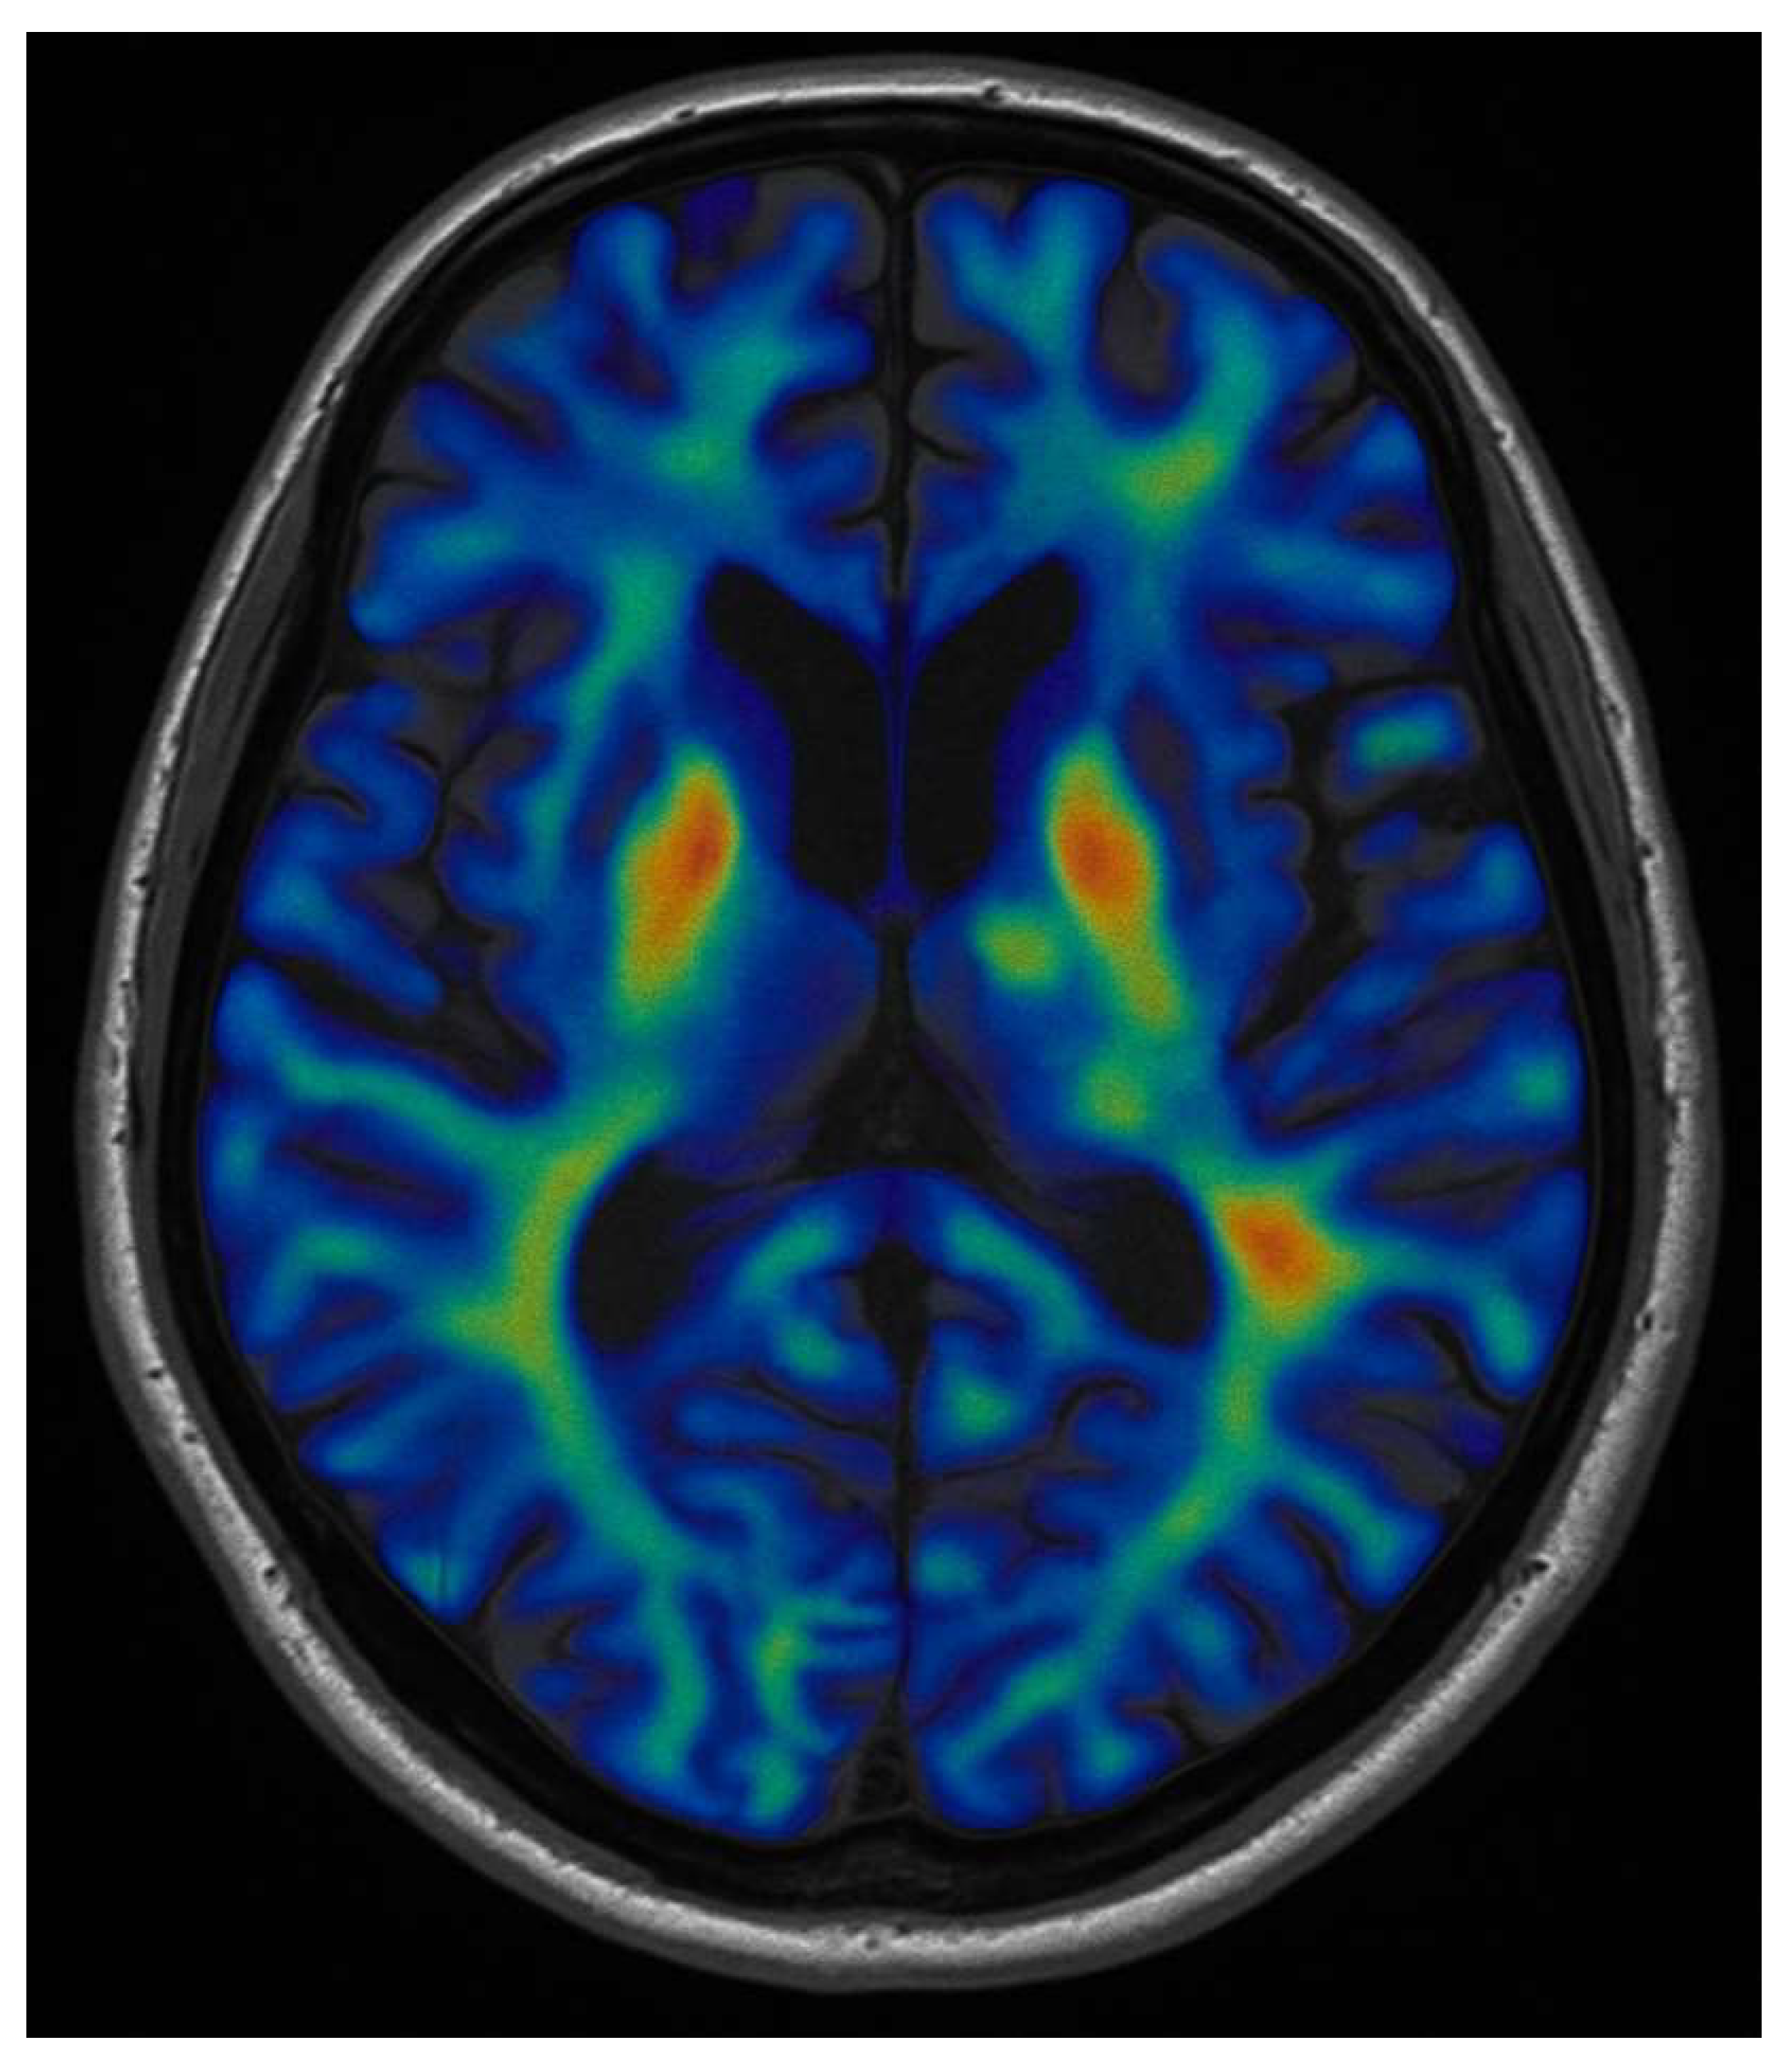

2.1. Task-Based fMRI for Functional Localization

2.2. Resting-State fMRI and Network Mapping

| Resting-State fMRI (rs-fMRI) | Analyses spontaneous BOLD signal fluctuations to infer functional connectivity without active tasks. | Suitable for patients unable to perform tasks; reveals intrinsic network organisation and compensatory plasticity. | Reduced specificity compared with task-based paradigms; sensitive to motion artefacts and haemodynamic disturbances in tumoural tissue. | Provides complementary information on network-level reorganisation and helps guide functional preservation strategies. |